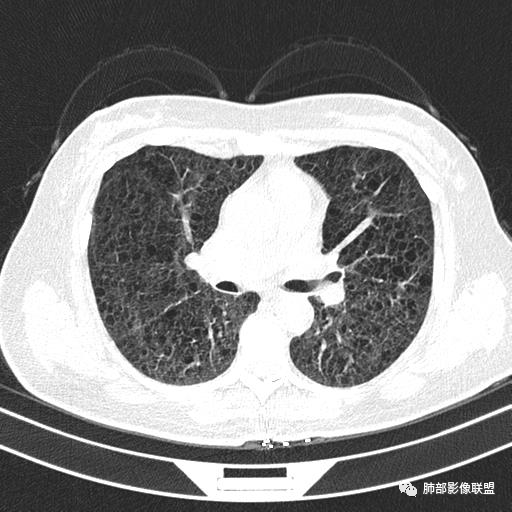

双肺弥漫囊腔,累及肋膈角,囊腔形态相对规则单一。

CT平扫示双肺弥漫分布大小不等囊状薄壁透光区,无内、中、外带分布差异,间质稍示增厚。拟LAM

中年女性育龄期妇女,咳嗽气喘,无吸烟史,有苯吸入史。影像:双肺弥漫均匀小囊腔,无明显分布优势,囊腔形态欠规则,壁薄,部分囊腔边缘血管征,伴双肺弥漫磨玻璃影,无结节,考虑lam,鉴别苯中毒肺损伤,囊腔多有分布优势,小叶中心分布为主,形态规整等

女,46,活动性气喘1年。苯吸入史半年。胸部CT:两肺弥漫囊腔,上至肺尖,下至肋膈角,形态类似小囊腔。考虑:LAM,鉴别LIP,BHD,PLCH等。

CT表现:双肺弥漫大小不等的薄壁囊腔,囊壁<2mm,外形规则,血管影多位于囊腔周围,囊腔之间肺组织正常,随着疾病进展到晚期,囊腔变大、增多,不可胜数,囊腔可融合成较大的囊,与肺气肿相似,形成间质性肺纤维化。部分病例可出现结节影。